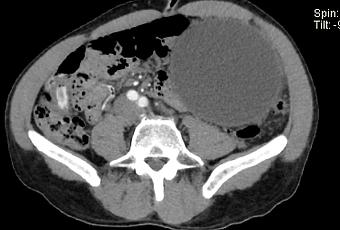

producen por la alteración de la estructura del conducto pancreático con la consiguiente pérdida y acumulación de jugo pancreático que da lugar a una necrosis grasa hemorrágica. No están revestidos por epitelio (por lo tanto, “pseudoquistes”), sino que una reacción inflamatoria grave da como resultado la encapsulación del quiste por tejido de granulación fibrosado. Esto suele tardar de 4 a 6 semanas 8,9 . En aproximadamente el 50% de los casos, el quiste conserva una comunicación con el conducto pancreático 2 . Estos quistes son más problemáticos de tratar y es más probable que reaparezcan.